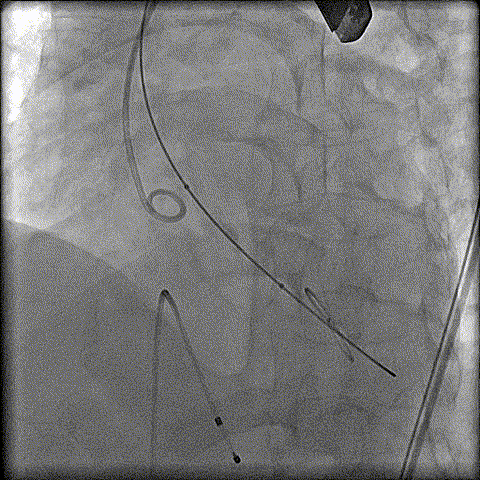

预扩

猪尾中部释放

稳定回收

评估

最终释放

后扩

无瓣周漏